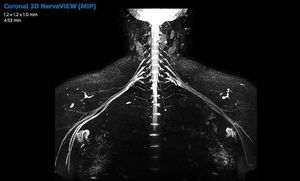

Non-invasive nerve plexus MR imaging

Mr Neurography

Plexus Imaging